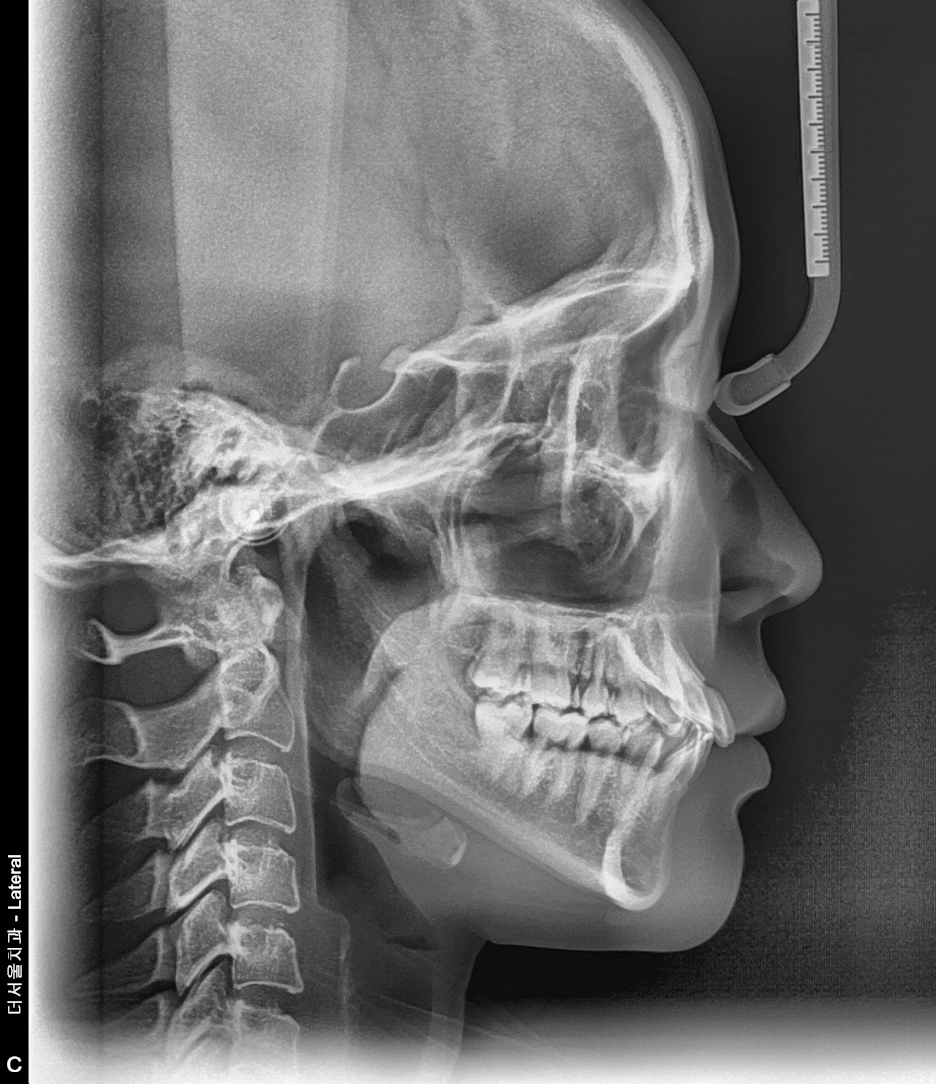

중첩시킨, 측면 두부 방사선 사진을 보면 확연히 앞니들의 기울기가 변화되는 것을

한 눈에 보실 수 있죠? 아래에는 참조 자료를 남깁니다.

왼쪽 사진은, 교과서에서 볼 수 있는 이상적인 위치의 앞니 기울기입니다.

물론 돌출입 을 따졌을 때는 비순각의 크기 또한 같이 고려를 해야 되나

해당 자료는 치아의 문제로만 바라보는 자료입니다.

오른쪽 사진으로는, 치아를 이동시키는 GIF 인데 이렇게 치근의 위치는 변화되지 않은 채

치축만 변화를 주는 경우가 있고 치근의 위치와 같이 기울기를 함게 변화를 주는 경우가

있습니다. 물론, 둘 다 같이 변화를 주는게 교정 치료 기간은 늘어날 수 있으며

어떤 것이 더 좋냐 라는 질문에서는, ‘환자의 구강 내 환경에 따라 다릅니다.’

라는 답변을 드릴 수 있겠네요.^^